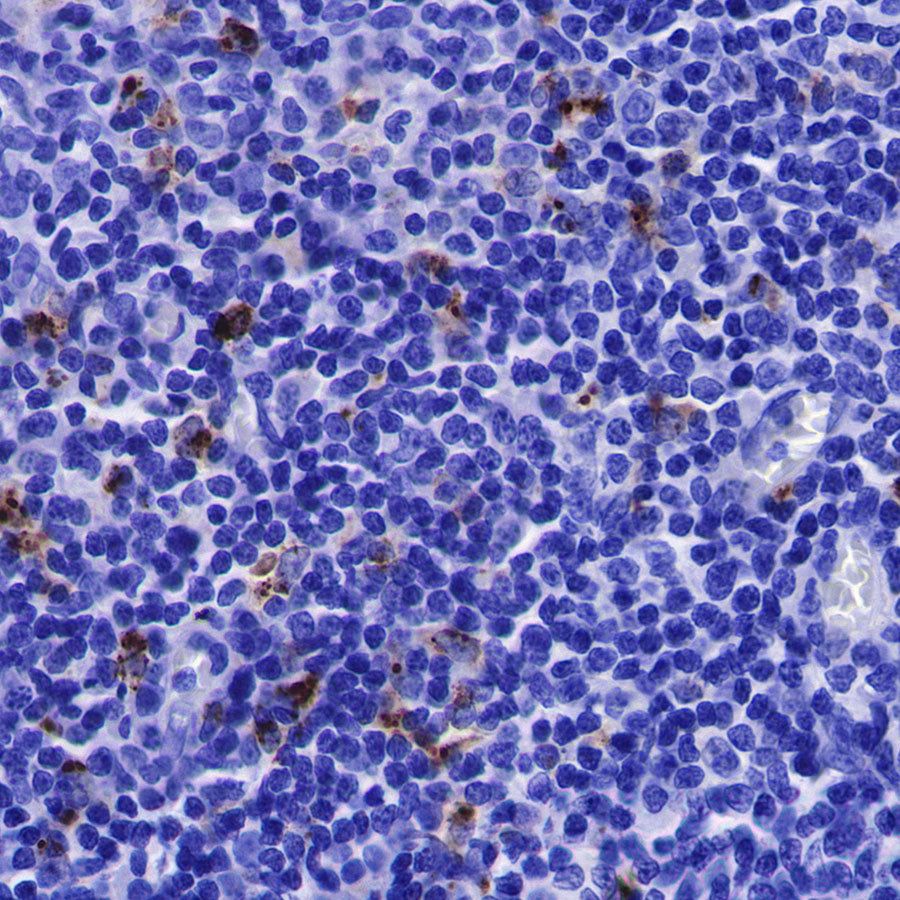

Immunohistochemistry

IHC shows positive staining in paraffin-embedded human tonsil. Anti-Lysozyme antibody was used at 1/100 dilution, followed by a HRP Polymer for Mouse & Rabbit IgG (ready to use). Counterstained with hematoxylin. Heat mediated antigen retrieval with Tris/EDTA buffer pH9.0 was performed before commencing with IHC staining protocol.